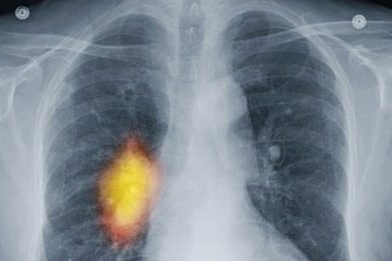

Ảnh chụp X-quang phổi của một người bị ung thư, khối u ung thư có màu vàng

Nếu các tế bào của khối u không lây lan và phát triển thì gọi là u lành tính, chúng không phải ung thư và thường có thể loại bỏ được. Ngược lại nếu các tế bào có thể xâm nhập vào các mô hoạc các cơ quan khỏe mạnh, hoặc lây lan khắp cơ thể qua máu hay hệ bạch cầu và liên tục phát triển mạnh thì các khối u này là u ác tính hay còn gọi là ung thư. Lúc này các tế bào ung thư sẽ lây lan nhanh hơn nếu khối u không được điều trị.